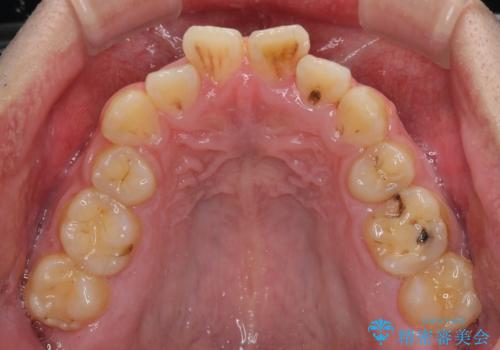

後戻りでデコボコの前歯 インビザライン矯正治療

- 高校時代に行った抜歯矯正が後戻りをしたとのことで来院された患者様です。

再矯正であることから、目立ちにくい装置を希望されたため、インビザラインにて矯正治療を行うこととしました。

下顎骨が左側に変位しているため、正中が合わないことは予想できましたが、歯列が整った後も咬み合わせが安定せず、咬み合わせを落ち着かせるために1年以上の期間を要しました。

噛みにくさの改善に時間がかかってしまうことがインビザラインの欠点の1つといえます。